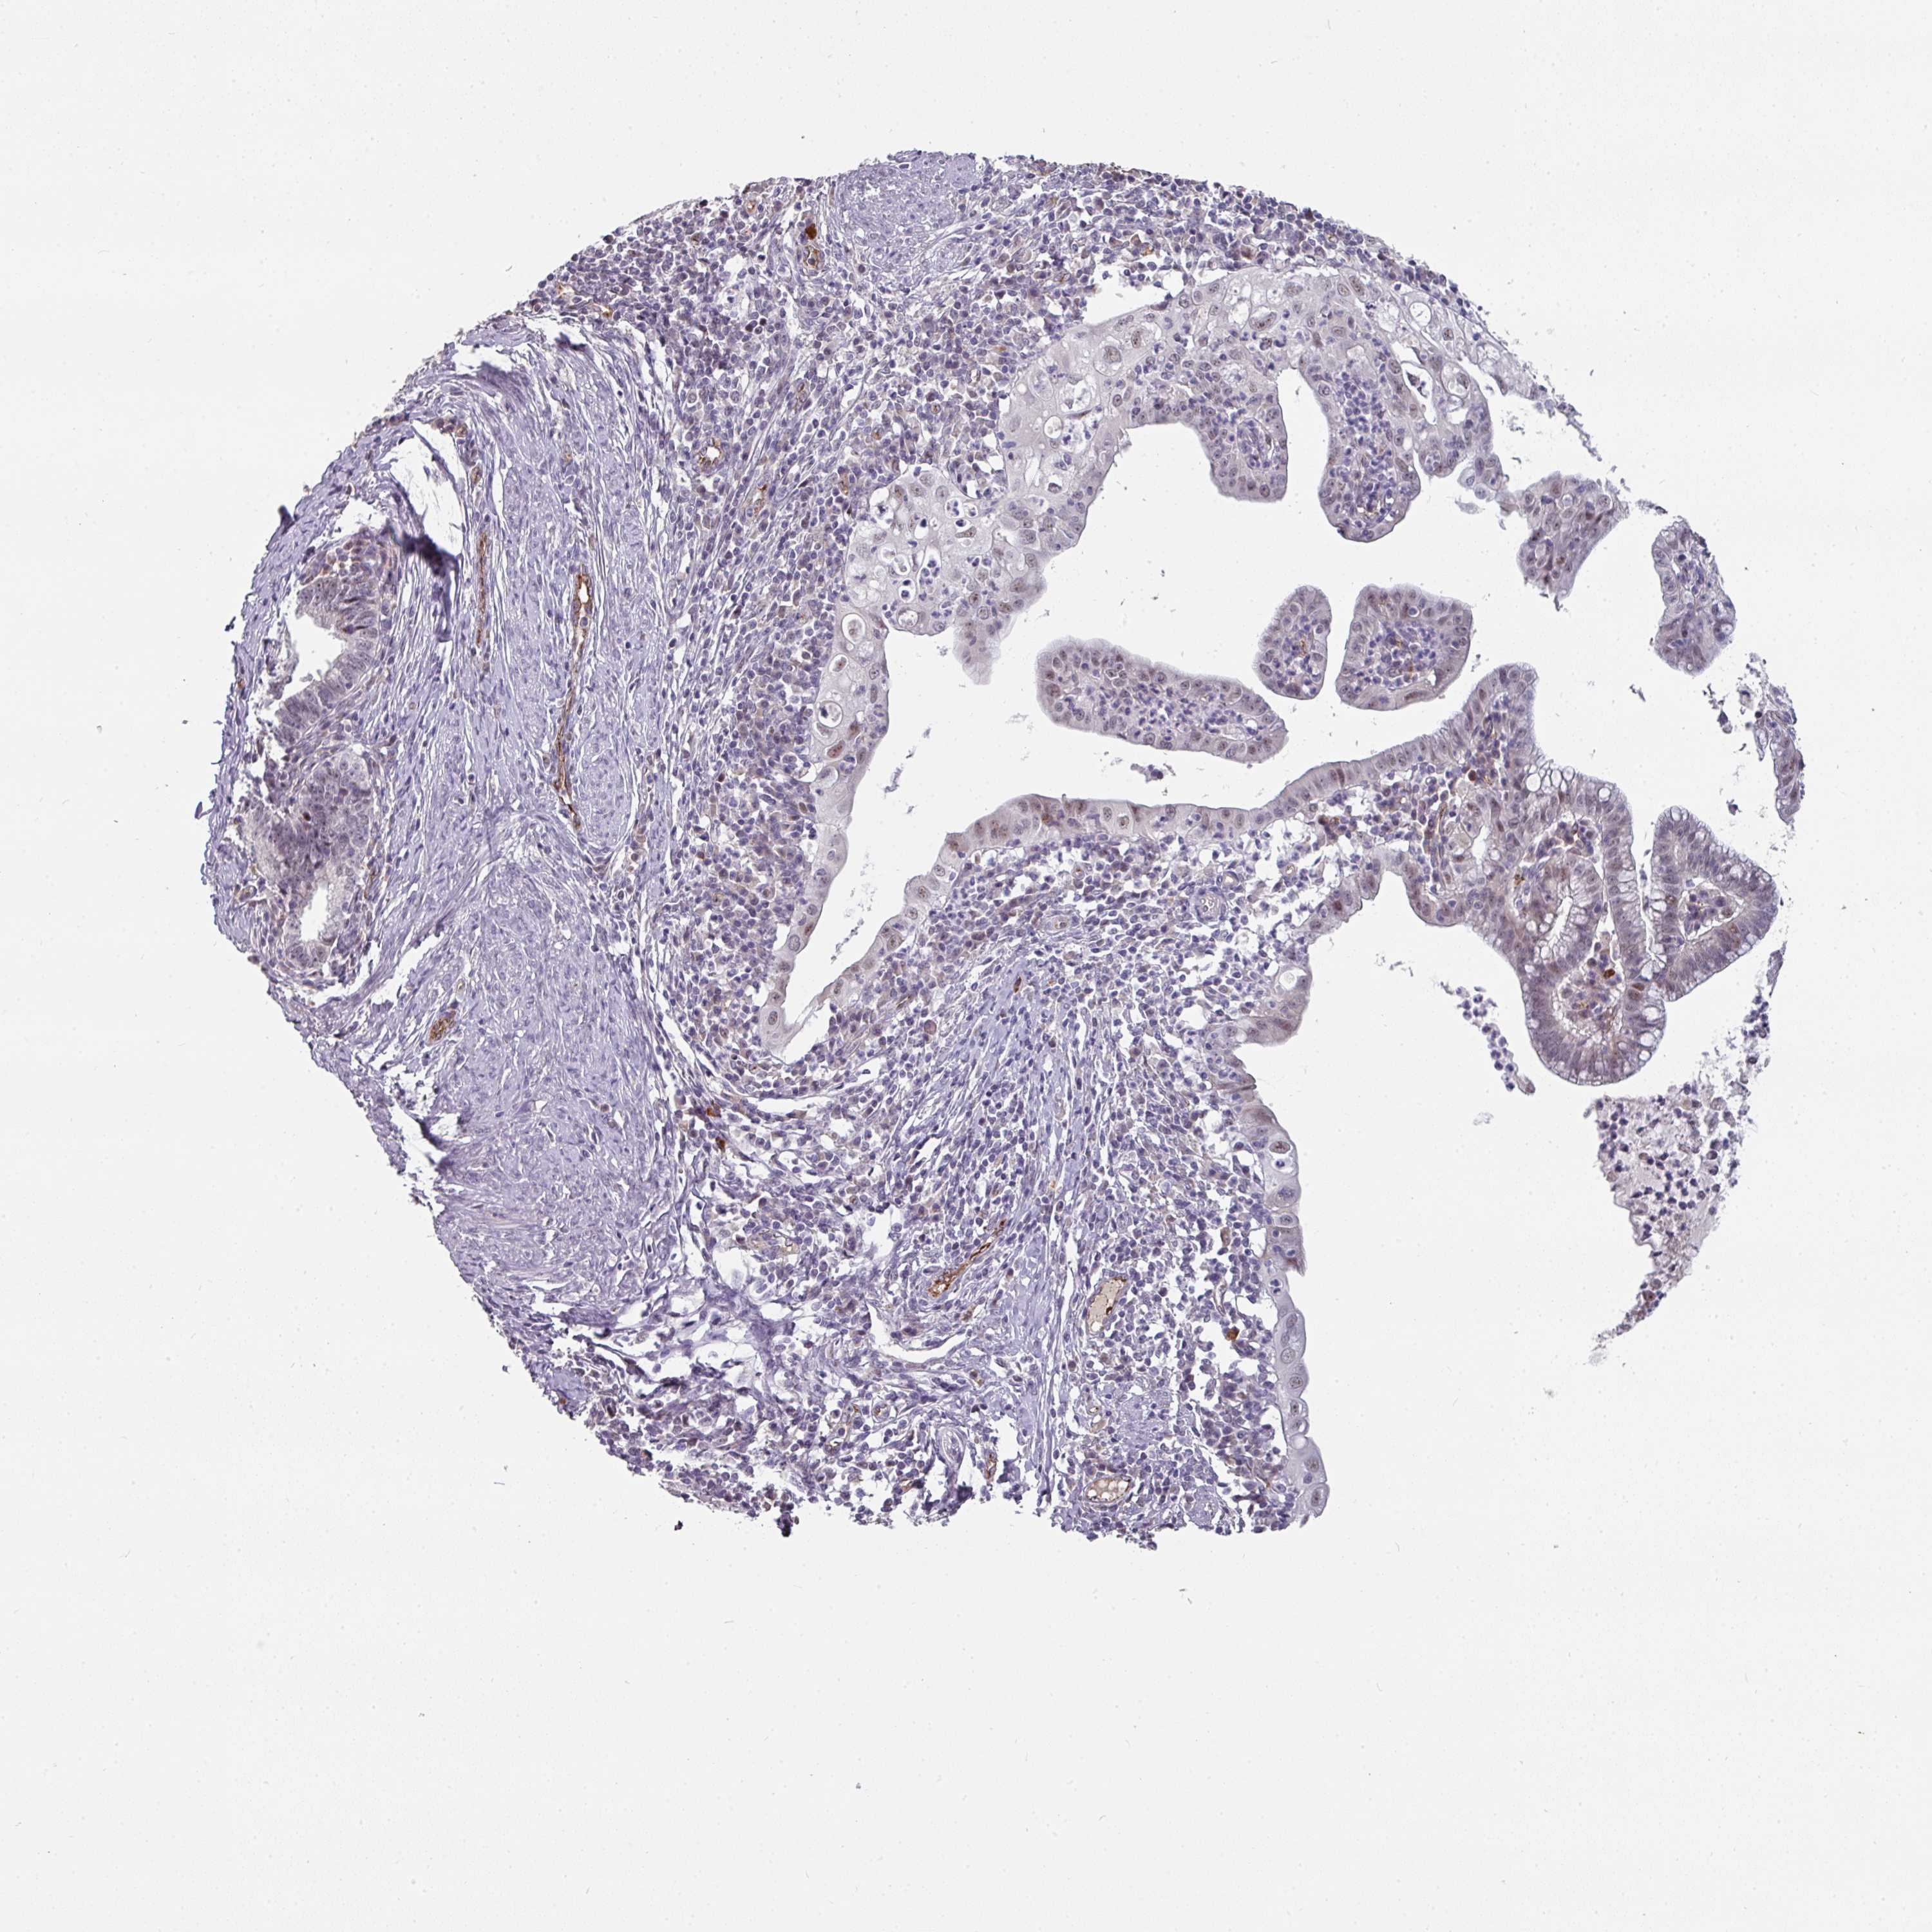

CERVICAL CANCER - Protein expressioni

A mouse-over function shows sample information and annotation data. Click on an image to view it in a full screen mode. Samples can be filtered based on level of antibody staining by selecting one or several of the following categories: high, medium, low and not detected. The assay and annotation is described here.

Note that samples used for immunohistochemistry by the Human Protein Atlas do not correspond to samples in the TCGA dataset.

Antibody stainingi

Antibody staining in the annotated cell types in the current human tissue is reported as not detected, low, medium, or high, based on conventional immunohistochemistry profiling in selected tissues. This score is based on the combination of the staining intensity and fraction of stained cells.

Each image is clickable and will lead to virtual microscopy that enables deeper exploration of all samples and also displays staining intensity scores, fraction scores and subcellular localization as well as patient and tissue information for each sample.

Antibody HPA052352

Staining

High

Medium

Low

Not detected

Intensity

Strong

Moderate

Weak

Negative

Quantity

>75%

75%-25%

<25%

None

Location

Nuclear

Cytoplasmic/membranous

Cytoplasmic/membranous,nuclear

Squamous cell carcinoma, NOS

Adenocarcinoma, NOS